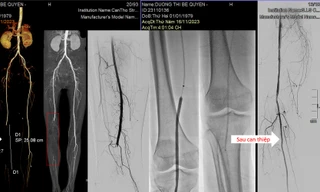

TPO - Một trường hợp nguy kịch vừa được các bác sĩ Bệnh viện Đa khoa Xuyên Á (TP.HCM) cứu sống đã gióng lên hồi chuông cảnh báo về một bệnh lý còn ít người biết đến nhưng có thể gây hoại tử, đoạn chi và tử vong, đó là căn bệnh Tắc tĩnh mạch chậu – đùi cấp do huyết khối.

TPO - Sau những cơn đau nhức dữ dội, chân phải của người bệnh dần tím tái, có dấu hiệu hoại tử. Qua chẩn đoán hình ảnh, các bác sĩ xác định mạch máu của người bệnh bị tắc, nguy cơ phải đoạn chi. Các bác sĩ đã nỗ lực can thiệp, tái thông mạch máu, giúp người bệnh thoát cảnh tàn phế.